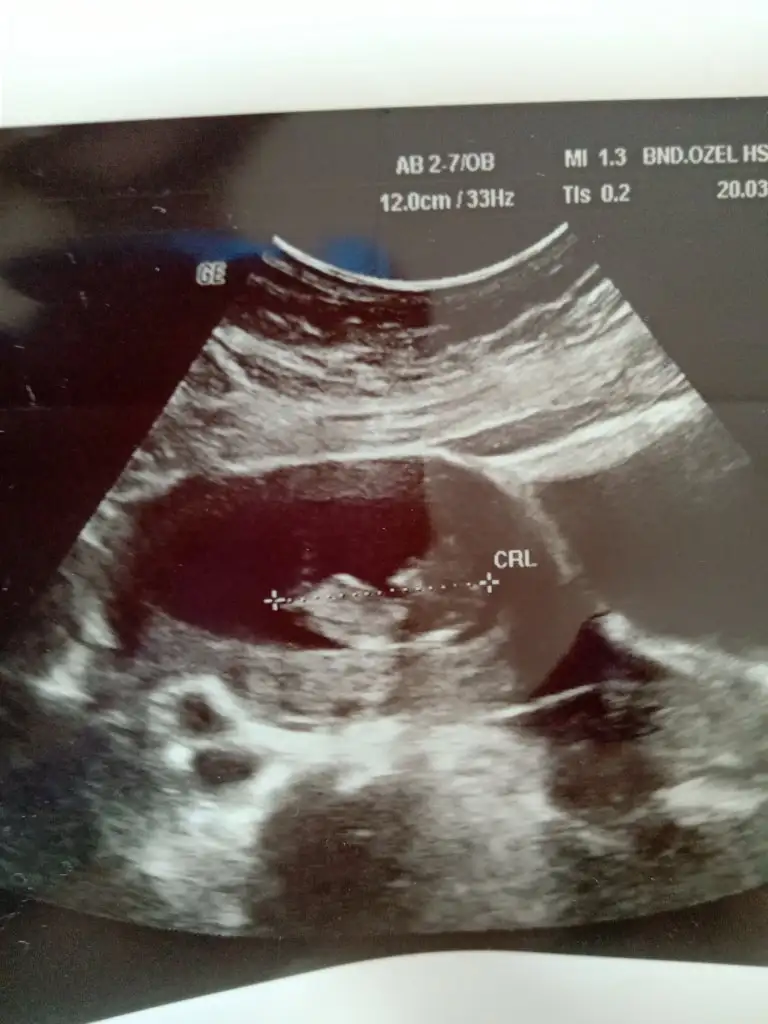

Net değil 12 13 haftada paylaşın sanki eminde değilim erkek gibi gibi![]()

Dr +getirmiş sanki erkek gibi gibi siz 12 13 hafta usg de paylaşın emin olamadımMerhabalar bizde burda 11 haftadaydik bizede tahmin edebilirmisiniz rica etsem ❤

Dr +getirmiş sanki erkek gibi gibi siz 12 13 hafta usg de paylaşın emin olamadım

Erkek gibiBuda diğer pozu o gün ki ölçüm olmayan ters duruyordu bunda ondan çevirip çektim resmini bunda da belli olmazsa 12 gün sonra kontrolümüz var o zaman atarım 14 haftalık olacak kısmetse o zaman ❤Ikra meyra cvp için teşekkür ederim ❤ diğer konuya da 6 haftalık halini atmıştım ama görmemiş tiniz sizin tahminleriniz genel olarak tutuyor ❤

Evet inşallah yaşayan ilk olcakErkek gibiteşekkur ederim evet cogunluk tutuyor bazı usg lerde yanıltıyor bazen pozisyonları nubu değiştiriyor vs ilk bebekmi

Teşekkür ederim ben sizin sandım herkes siiz etiketleyinceRc ederim diger taraf benim konum degil ama orası aktifde değil arada etiket yapanlar var onlara cvp veriyorumbuna göre kız ama tutmayabilir kese konumu en iyi nub 11 12 13 haftalar olmalı